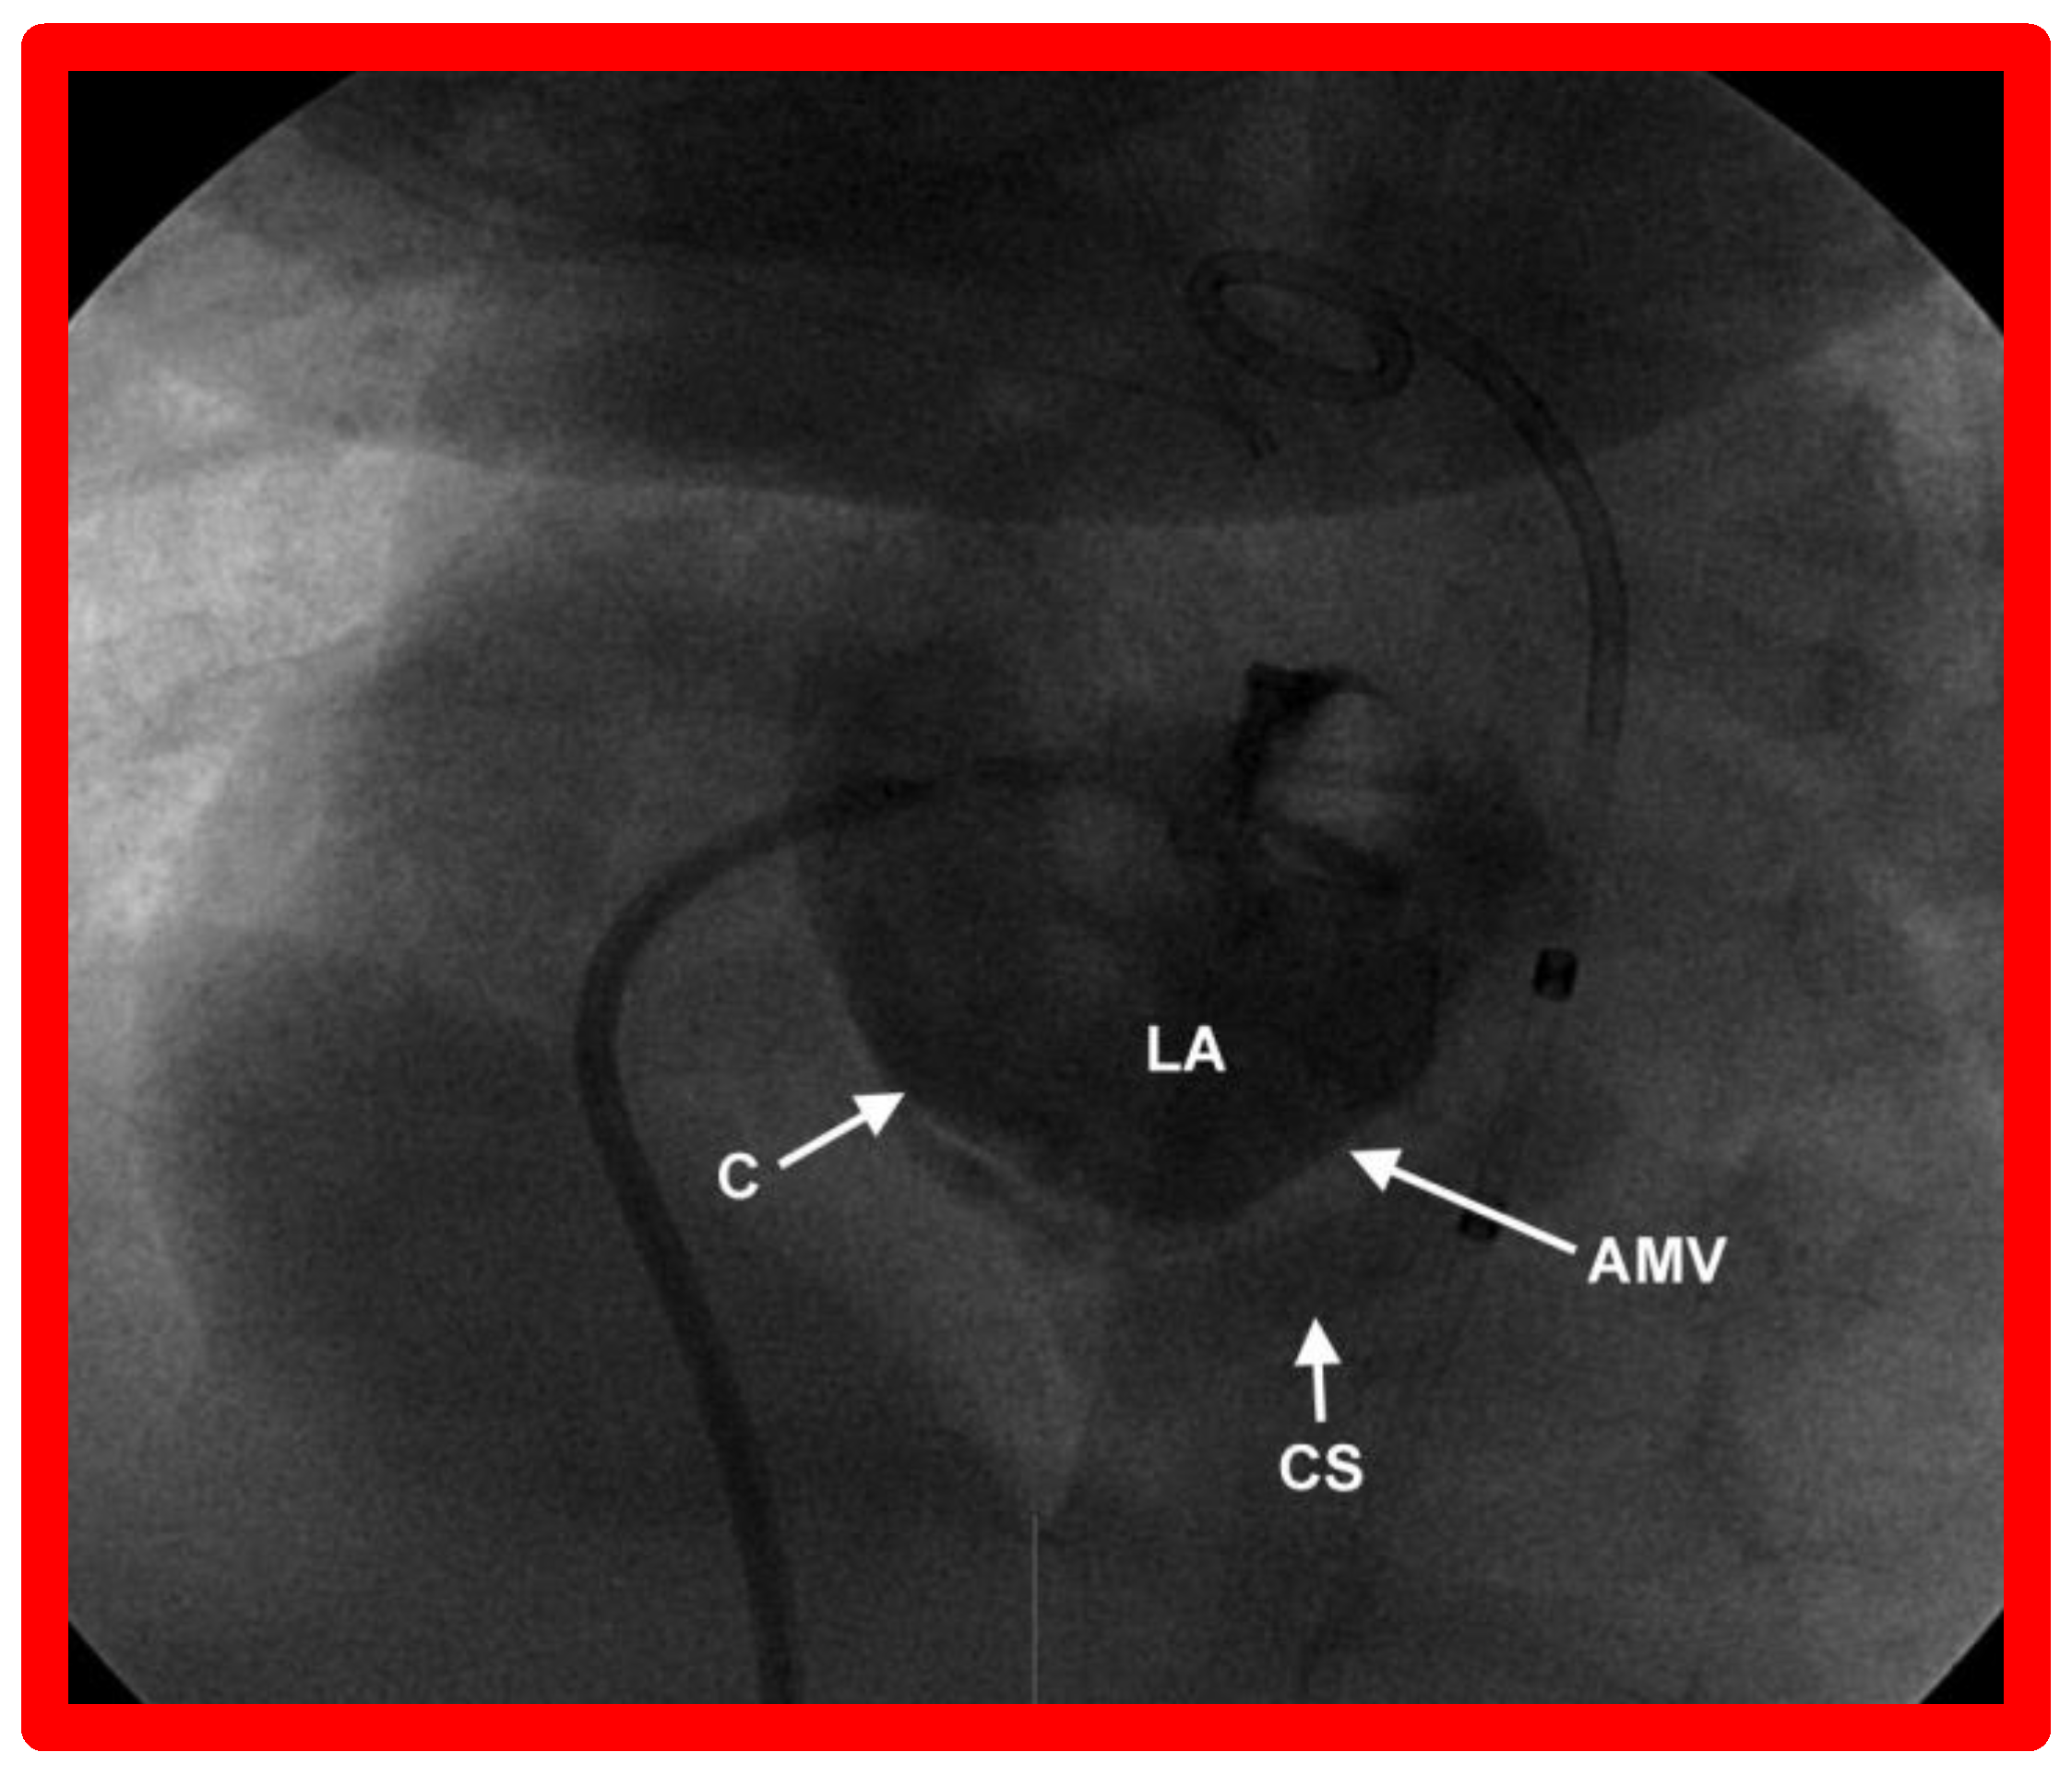

9. Cardiac Catheterization with Angiography, Magnetic Resonance Imaging (MRI) and Computed Tomography (CT)